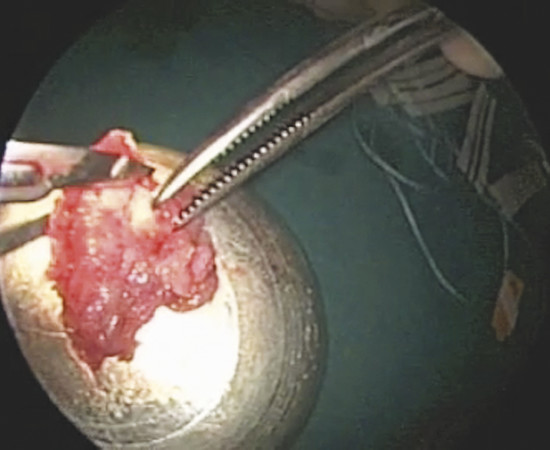

A mucoperiosteal graft is harvested from the inferior turbinate by an endoscopic turbinoplasty following Marks’ technique. 2 In particular, after injecting 2 to 3 mL of solution containing 1% Carbocaine with 1:80,000 epinephrine on inferior turbinate mucosa, over the bone, an incision on the head of the inferior turbinate with a number 15 blade along the inferior edge of the turbinate is performed. The mucoperiosteum of the nasal side of the turbinate is thus separated by a suction elevator from the underlying bone. The turbinate bone with attached lateral mucosa is then removed by endoscopic scissors till the tail of the turbinate; the residual bone can be outfractured to reduce the angle between the turbinate and lateral nasal wall. Finally the mucosa of the nasal side (previously elevated) is flipped over to cover the exposed area.

The removed part of the inferior turbinate (Fig. 19‑6) is therefore used to harvest the graft by separating the mucoperiosteum (lateral mucosa of the inferior turbinate) from the underlying bone (Fig. 19‑7). The mucoperiosteal graft is trimmed to size (minimum 1 cm of diameter larger than the perforation).